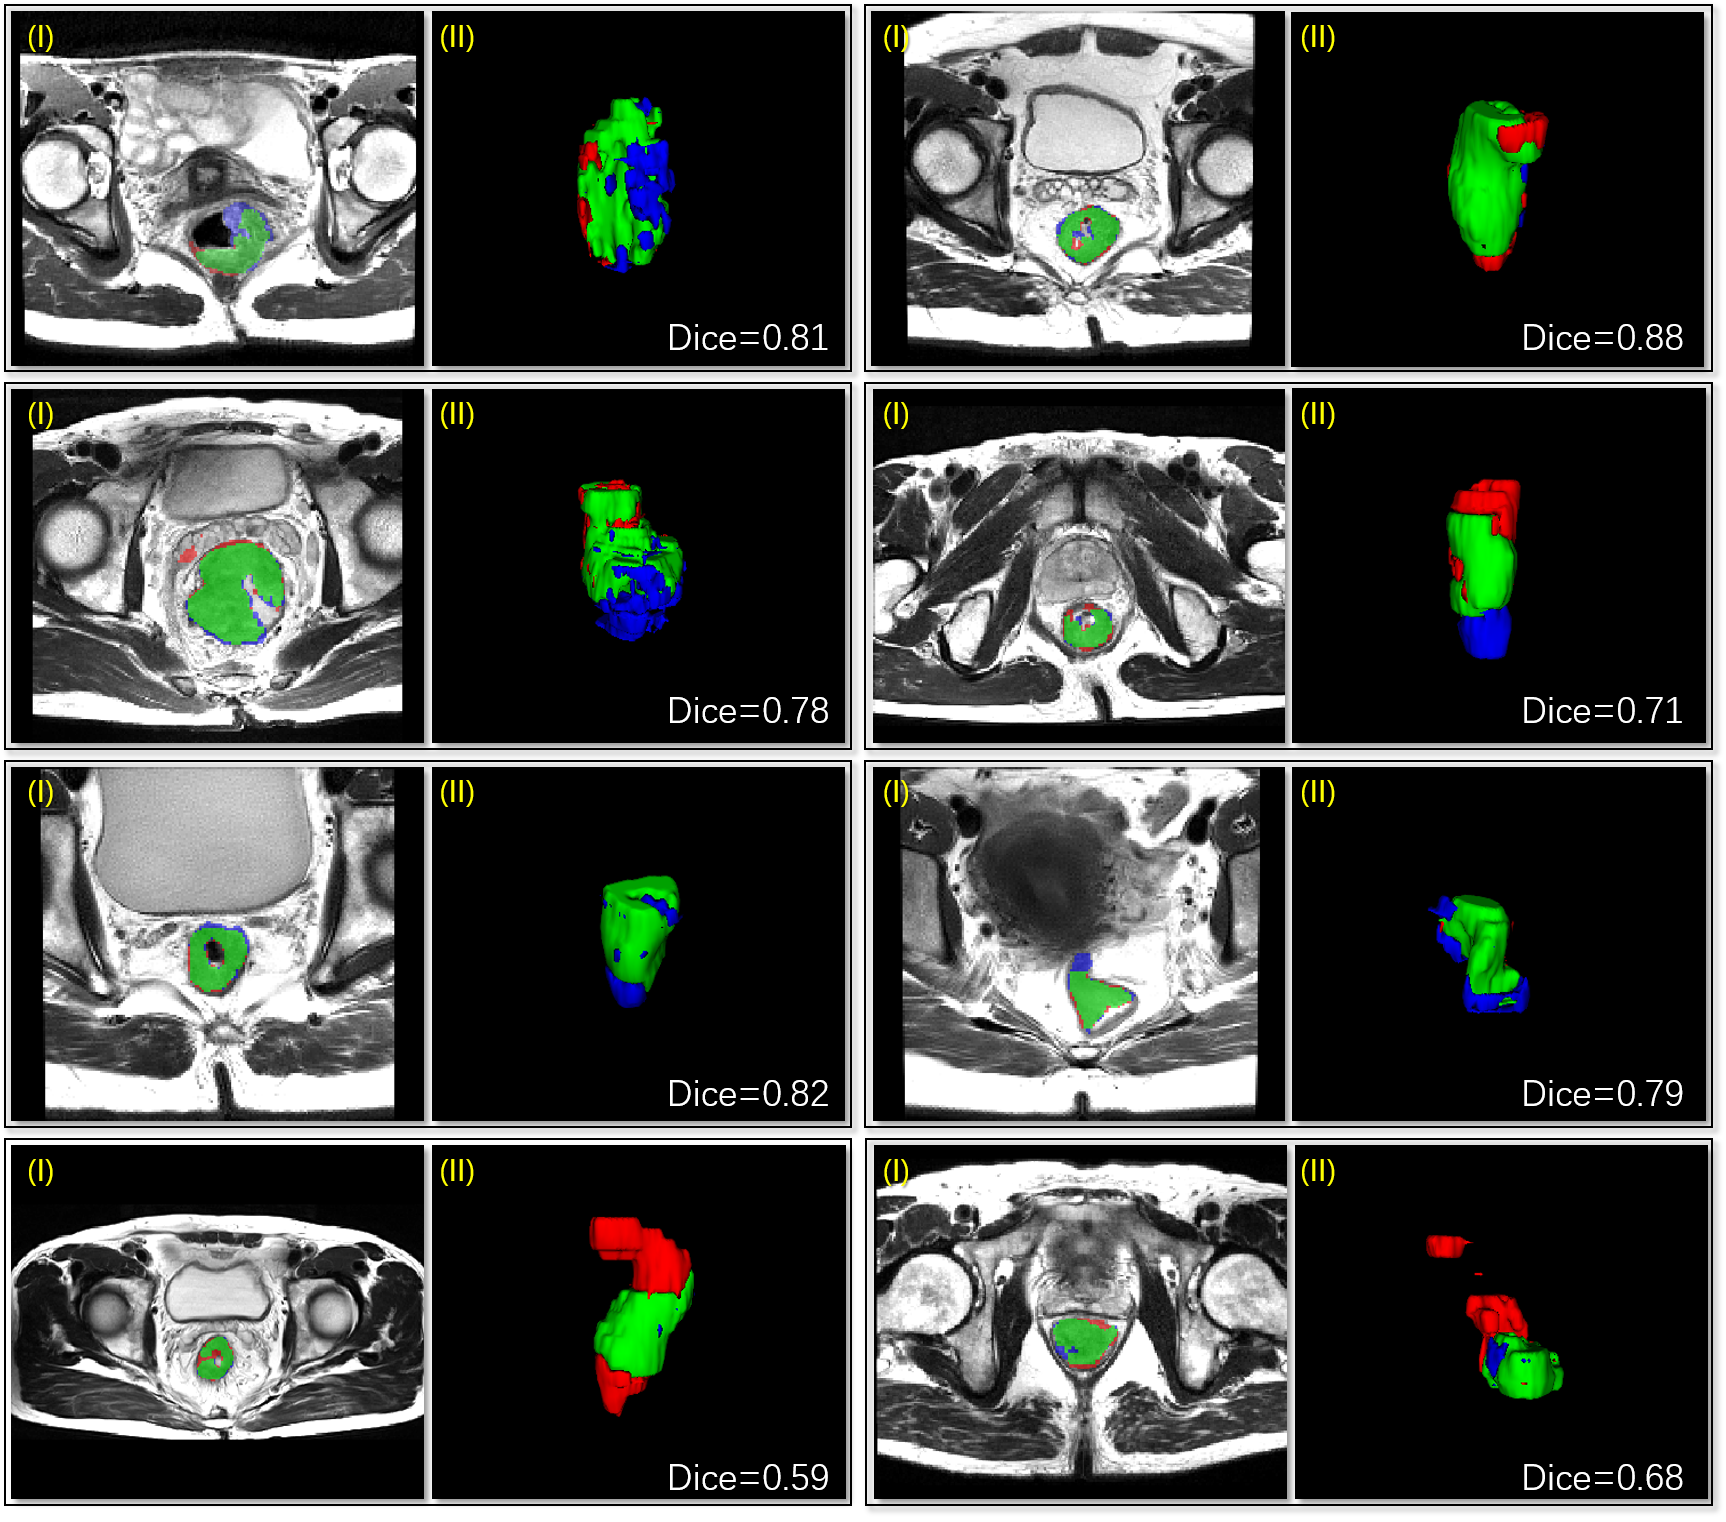

For evaluation, four-fold cross-validation was conducted on 64 scans and their mean scores are reported in TABLE. 2. Comparison of predicted masks between different methods is illustrated in Fig. 5; Eight volume predictions are illustrated in Fig. 6.

Additionally, a 3D-FPN based Mask R-CNN is evaluated. As the scores and figures illustrates, the limitation of 3D Mask R-CNN is two-fold: bad-shaped bounding boxes’ cutting off some parts of the objects, and low-resolution masks generated by the coarse-resolution feature maps of the FPN backbone.

Finally, we also set a super-voxel clustering based [4] method as the baseline. Without the merit of discriminative 3D deep features, super-voxels are inevitably over-segmented or under-segmented. In our experiments, one of the 64 targets went completely missing and significantly lowered the Dice score, while some wrong super-voxels were chosen as the output mask.